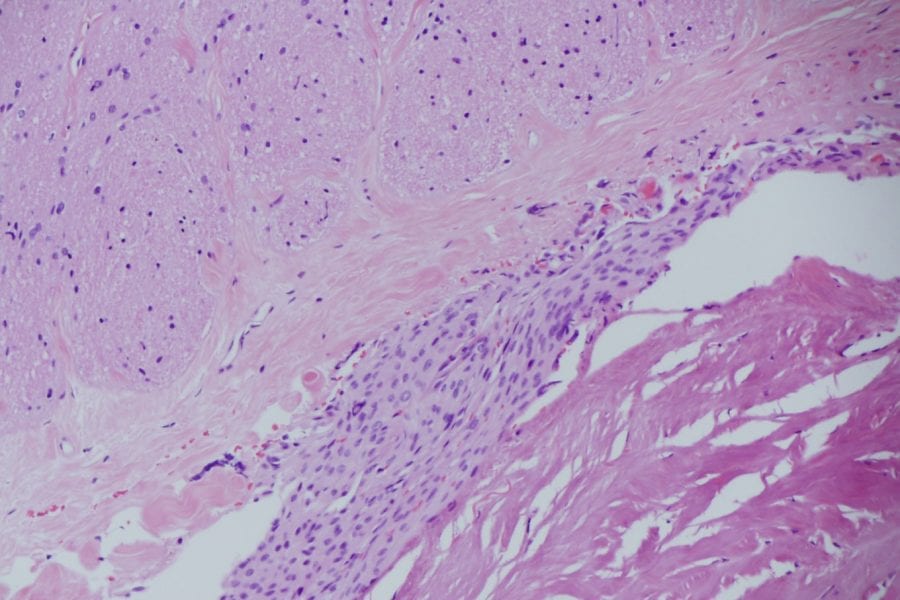

The new Zeiss Microscope was delivered to the St Vincent’s Private Hospital in January 2019. It is a superlative piece of engineering. The new microscope…